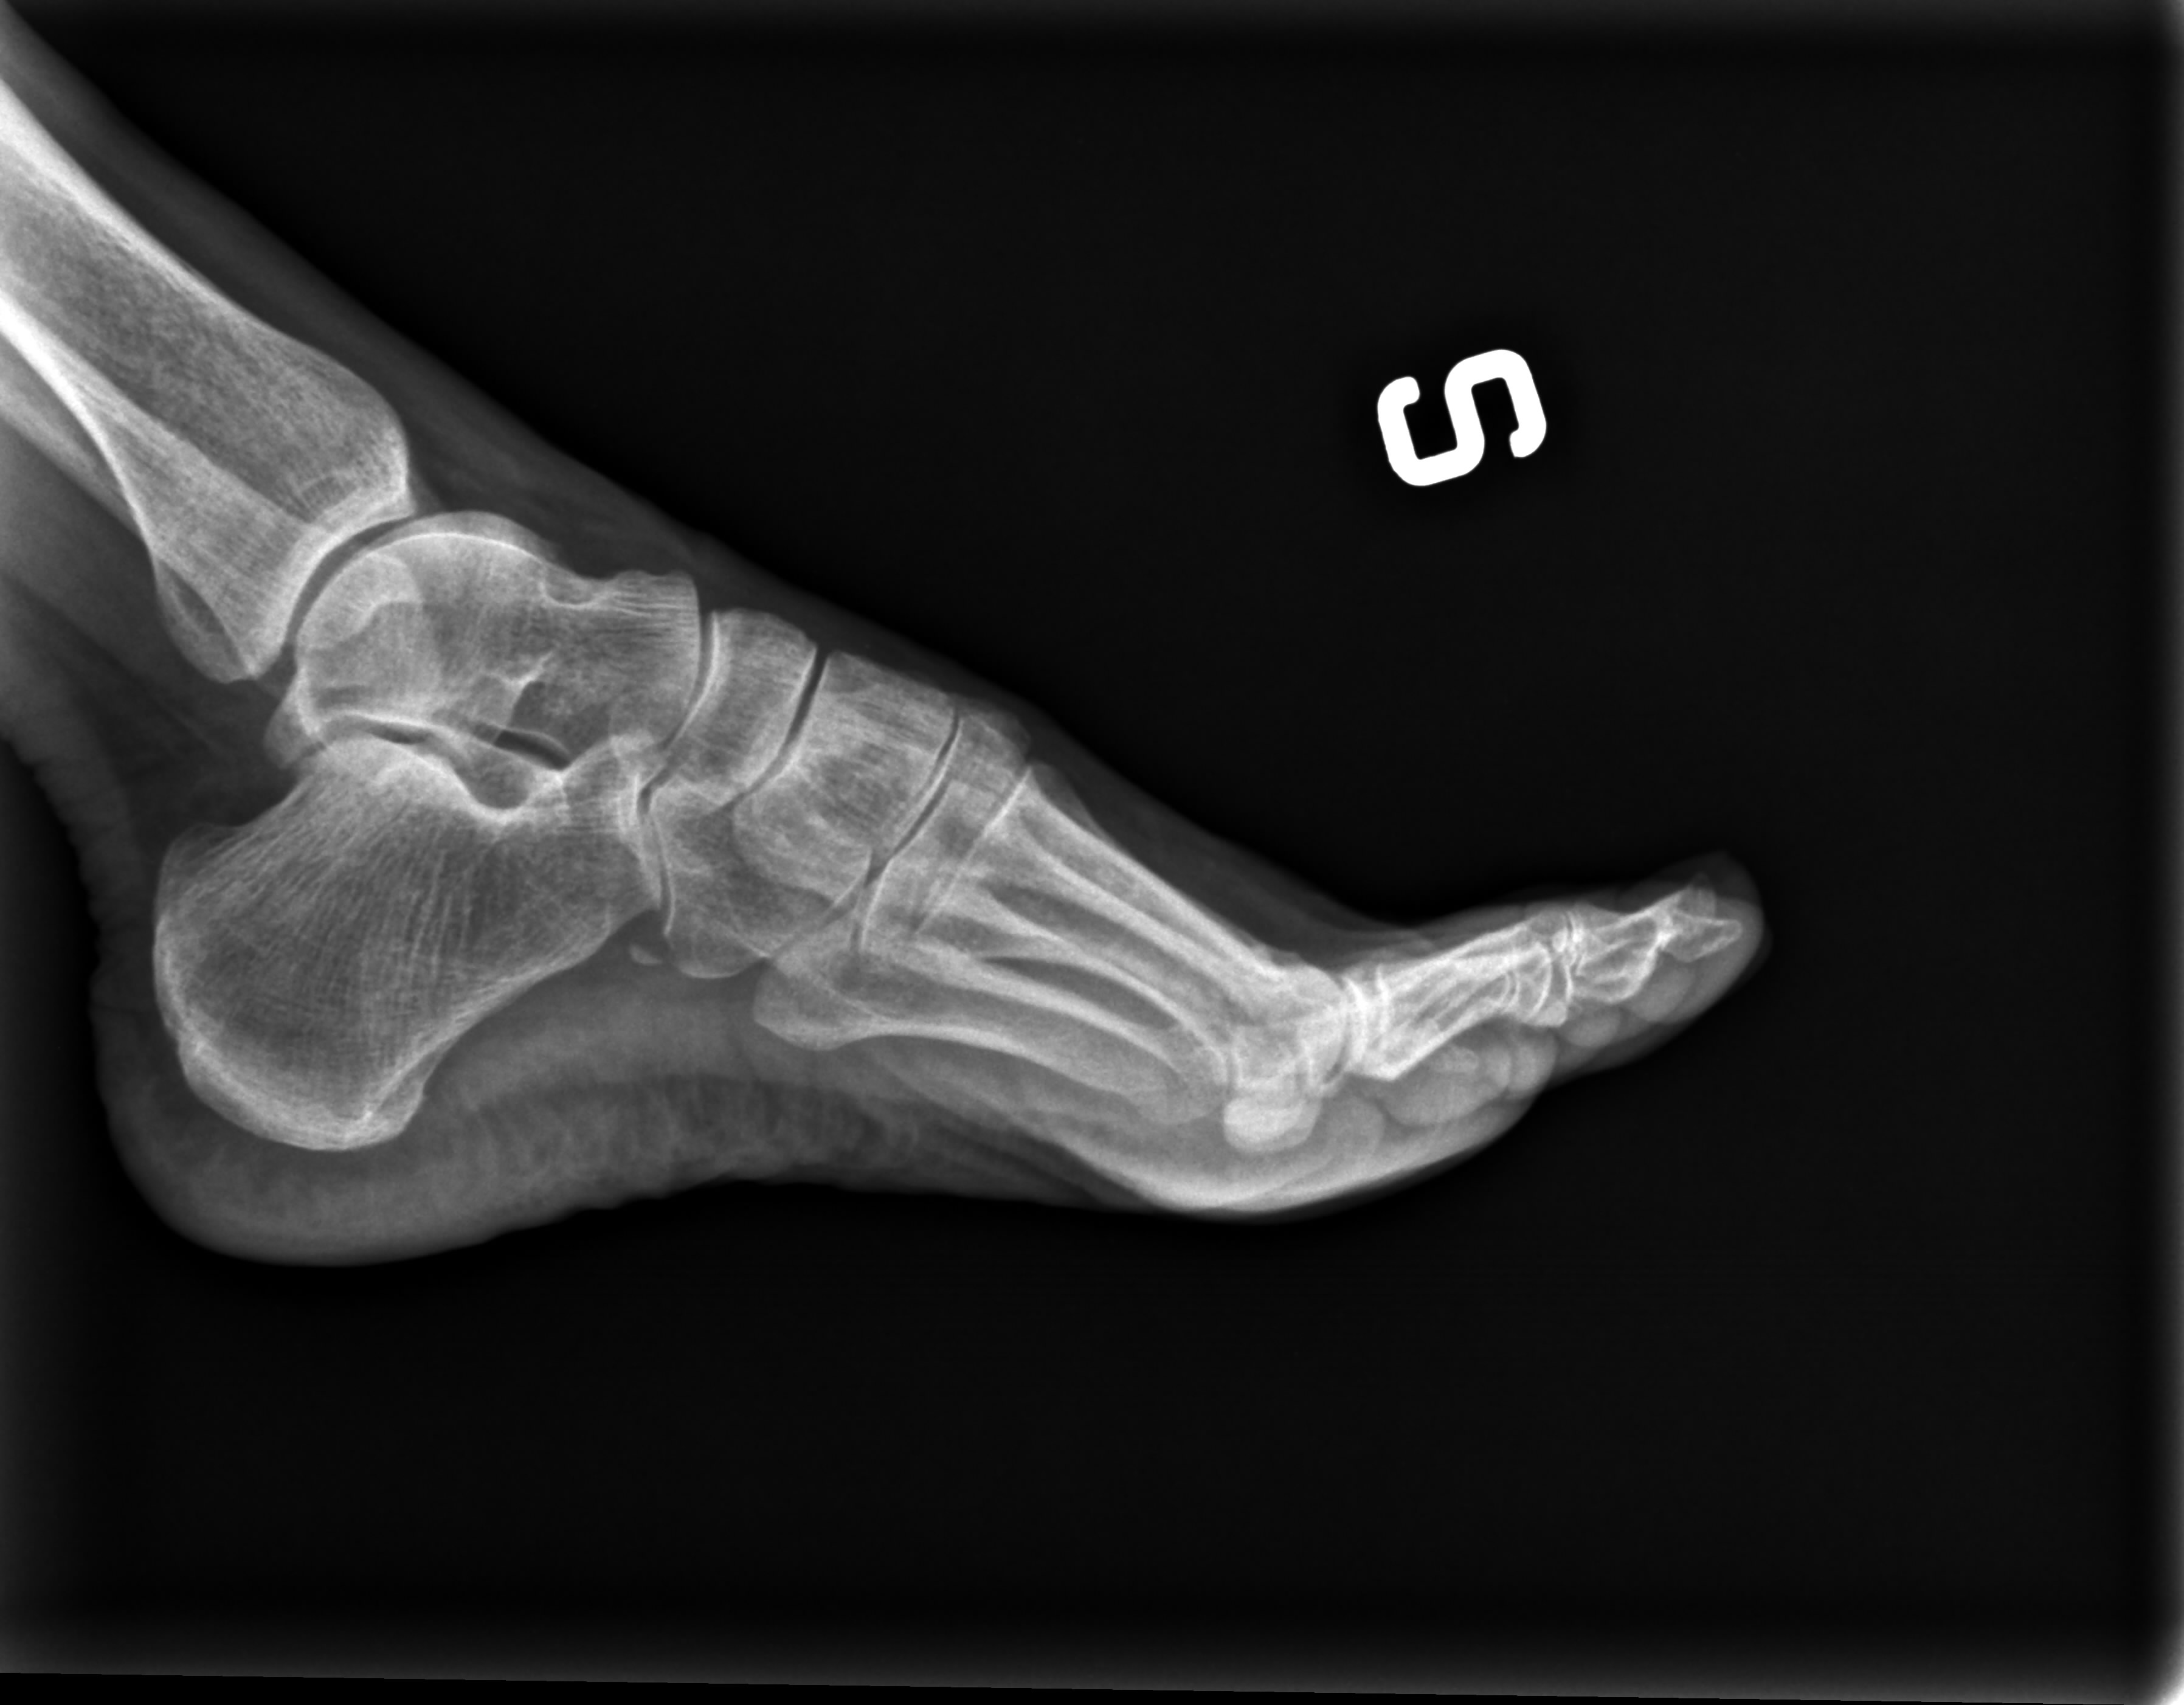

Buona sera vorrei una consultazione delle lastre che allego

per sapere se ho rotture ossee al piede .Saluti Rosi

2_0885679618r.aup.jpg

[ 377.62 KiB | Osservato 596 volte ]